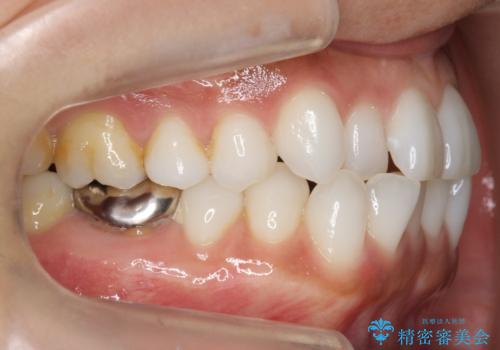

30代女性 前歯のがたつき

- 30代女性

- 矯正装置

- インビザライン

- 治療期間

- 1年5ヶ月

- 前歯のがたつきを主訴に来院。

右下の奥の銀歯も治療しています。

- 115.5万円 矯正治療 85万円、奥歯ジルコニアクラウン11万円(ZrCr 10万円、仮歯1万円、矯正用仮歯2万円)セラミックインレー7万円費用は治療当時の料金となります

下の前歯を下げるため、IPR(歯をわずかに削る処置)を行っています。